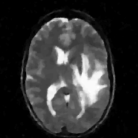

We study the performance of the proposed algorithms as a function of acceleration in the presence of noise in Fig. 3. We used a 512×512512512512\times 512 MRI brain image, sampled using a random sampling operator at different acceleration factors (R = 2.5, 4, 6, 8, 10 and 202020). The measurements were contaminated with complex white Gaussian noise of σ=10.2𝜎10.2\sigma=10.2. The PSNR and SNR as a function of accelerations of this experiment are plotted in Fig. 3, where we compare our method against DLMRI and TV. We observe that the proposed scheme provides a consistent improvement in the presence of noise.

The reconstructions of an ankle image from its 4 fold Cartesian undersampled Fourier data, corrupted with zero mean complex Gaussian noise with a standard deviation σ=10𝜎10\sigma=10, are shown in Fig. 5. This is a really challenging case since the 1-D downsampling pattern is considerably less efficient than the 2-D random pattern used in the previous experiment. We observe that the non-local algorithm provides better reconstructions than the other schemes. Specifically, the TV scheme results in patchy artifacts. The DLMRI scheme results in blurring and loss of details close to the heel. The details are relatively better preserved close to the finger since there are no structures above or below it that aliases to it. By contrast to the classical algorithms, the degradation in performance of the non-local algorithm is comparatively small. The quantitative comparisons of the algorithms on this setting using different images are shown in the top section of Table IV.

The reconstructions of a 256×256256256256\times 256 brain image from its radial samples acquired with a 40 spoke trajectory are shown in Fig. 6. The measurements are corrupted with zero mean complex Gaussian noise of standard deviation σ=18.8𝜎18.8\sigma=18.8. All methods result in loss of subtle image features since the acceleration factor and the noise level are high. We observe that the NLS scheme provides better recovery than the competing methods. The quantitative results in this setting for various MR images are shown in the bottom section of Table IV. We observe that the SNR improvement offered by NLS over the other methods are not as high as in the previous cases, mainly due to the considerable noise in the data and the high acceleration.

Refer to caption

(a) PSNR vs Accelerations

(b) SNR vs Accelerations

Figure 3: SNR and PSNR vs Acceleration. We used a 512×512512512512\times 512 MRI brain image, sampled using a random sampling operator at different acceleration factors (R=2.5,4,6,8,10 and 20). The measurements were contaminated with complex white Gaussian noise of σ=10.2𝜎10.2\sigma=10.2. The SNR of the reconstructions obtained using the three algorithms are plotted. These results show that the NLS scheme is capable of providing better reconstructions at a range of accelerations. Specifically, it provides a consistent improvement of 0.5-9 dB in SNR/PSNR over the other algorithms.